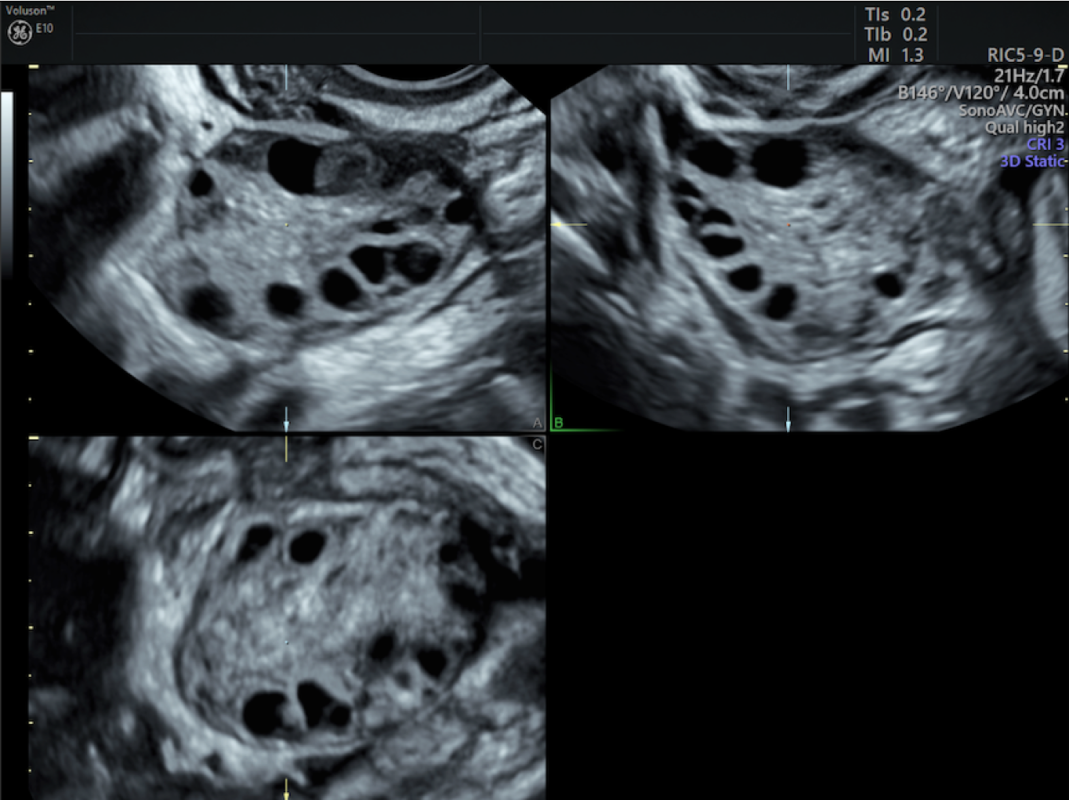

I’ve been struggling with chronic pcos since I was a teenager. I am an adult now and the symptoms and side effects are worst. There is no cure found yet. I’ve been having more severe symptoms and it’s painful and uncomfortable. I have a hormonal disorder that has been causing me a lot of ovarian pain and infections. I have little to no support a struggling mother no medical and it’s been very hard to be able to pay for the surgery that’s needed to alleviate pain and growing discomfort and large cysts thank You and god bless